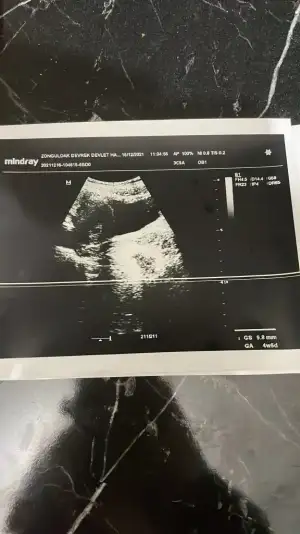

merhaba kızlar bende bir soru sormak istiyorum doktora gittim ultrasyon ile muayene etti iki ayrı ustrasyon kagıdı verdi birinde 4+5 9.1 mm birinde 4+6 9.8mm yazıyordu bu ne anlama geliyor kan degerinde 5355 cıkmıstı doktor bi acıklama yapmadı ikiz olma durumu varmıdır size nasıl kahıt vermişlerdi hatırlıyormusunuz

O Mm kesenin boyutudur. Henüz bebek bile oluşmamış olur bu haftada. 2 hafta sonra giderseniz daha net bilgiler elde edersiniz